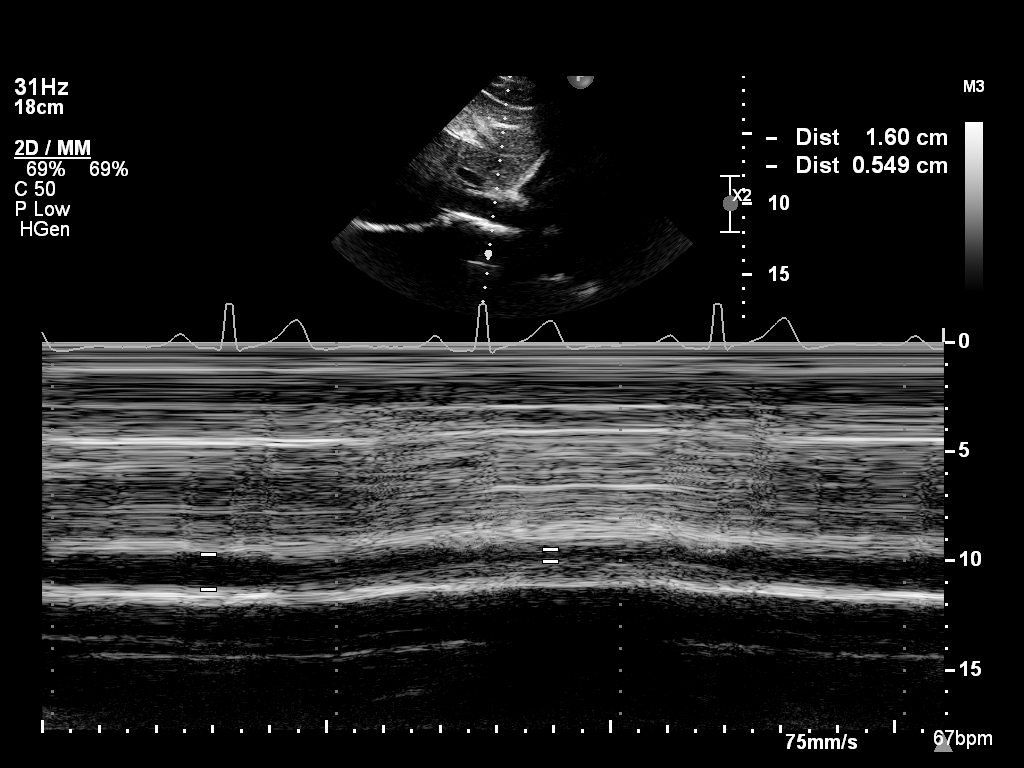

mmode-a4ch-rv mmode-a4ch-rv M-mode for measuring TAPSE

mmode-ivc mmode-ivc M-mode of the inferior vena cava

mmode-plax-av mmode-plax-av M-mode of the aortic valve in PLAX

mmode-plax-lv mmode-plax-lv M-mode in PLAX focused on LV walls

mmode-plax-mitral mmode-plax-mitral M-mode in PLAX focused on the mitral valve